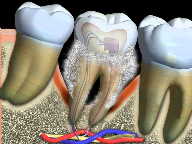

Teeth are covered in a hard, outer coating called enamel. Every day, a thin film of bacteria called dental plaque builds up on your teeth. The bacteria in plaque produce acids that can begin to harm enamel. Over time, the acids can cause a hole in the enamel. This hole is called a cavity. Brushing and flossing your teeth can protect you from decay, but once a cavity happens, a dentist has to fix it.

Gingivitis is the first stage of Periodontal disease. Plaque, (a sticky substance filled with bacteria) settles along the gum line of the teeth and causes the gums to swell, become red in appearance and bleed.

If the plaque is not removed, bacteria settles around the roots of the teeth and starts to destroy the supporting bone. The bone loss is not reversible. The gums become infected and pull away from the teeth, forming pockets.

As the pockets become deeper and the infection progresses, more bacteria accumulate and further bone loss occurs. The gums shrink away and the teeth start to become loose and may shift. Many people suffer from bad breath at this stage.

When periodontal disease has reached its advanced stage, painful abscesses can form in the gum. There is very little bone support left and the teeth are loose. In most cases, teeth that have reached this stage require extraction.